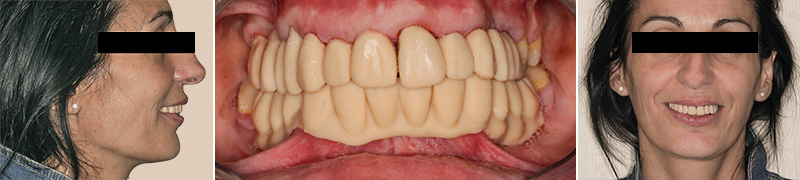

Les restaurations finales maxillaires ainsi que les chapes mandibulaires ont été essayées et assemblées à l’aide d’un CVIMAR. Après assemblage des chapes porteuses d’attachements, les prothèses amovibles d’usage ont été essayées puis délivrées à la patiente.

Pour garantir une bonne fonction, une occlusion bilatéralement équilibrée a été mise en place. Une période de 15 jours a été respectée avant le scellement des parties femelles dans l’intrados de la prothèse maxillaire.

Fig. 12 : assemblage des prothèses d’usage.